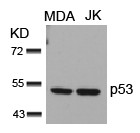

Produktinformationen "Anti-p53"

Protein function: Acts as a tumor suppressor in many tumor types, induces growth arrest or apoptosis depending on the physiological circumstances and cell type. Involved in cell cycle regulation as a trans-activator that acts to negatively regulate cell division by controlling a set of genes required for this process. One of the activated genes is an inhibitor of cyclin-dependent kinases. Apoptosis induction seems to be mediated either by stimulation of BAX and FAS antigen expression, or by repression of Bcl-2 expression. In cooperation with mitochondrial PPIF is involved in activating oxidative stress-induced necrosis, the function is largely independent of transcription. Induces the transcription of long intergenic non-coding RNA p21 (lincRNA-p21) and lincRNA- Mkln1. LincRNA-p21 participates in TP53-dependent transcriptional repression leading to apoptosis and seem to have to effect on cell-cycle regulation. Implicated in Notch signaling cross-over. Prevents CDK7 kinase activity when associated to CAK complex in response to DNA damage, thus stopping cell cycle progression. Isoform 2 enhances the transactivation activity of isoform 1 from some but not all TP53-inducible promoters. Isoform 4 suppresses transactivation activity and impairs growth suppression mediated by isoform 1. Isoform 7 inhibits isoform 1-mediated apoptosis. Regulates the circadian clock by repressing CLOCK-ARNTL/BMAL1- mediated transcriptional activation of PER2 (PubMed:24051492). [The UniProt Consortium]

| Anwendung: | WB, IHC (paraffin), ICC, IF |

| Immunogen: | Peptide sequence around aa.13~17 (P-L-S-Q-E) derived from Human p53 |